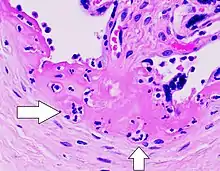

- Villitis, inflamación de las vellosidades coriónicas.

La vilitis de etiología desconocida (VUE, del inglés Villitis of unknown etiology), también conocida como vilitis crónica, es una lesión placentaria. La VUE es una condición inflamatoria que involucra las vellosidades coriónicas (vellosidades placentarias). Es una condición recurrente y puede estar asociada con la restricción del crecimiento intrauterino (RCIU). La RCIU implica el crecimiento deficiente del feto, la muerte fetal, el aborto espontáneo y el parto prematuro.[3][4] Se repite en aproximadamente 1/3 de los embarazos posteriores.[5]

La VUE es una lesión común caracterizada por inflamación en las vellosidades coriónicas placentarias. También se caracteriza por la transferencia de linfocitos maternos a través de la placenta.[4]